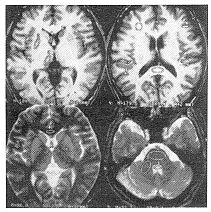

3.感兴趣区(ROI)设定:所有扫描均摄取横断面图像。ROI选择灰质12处,包括双侧额叶、颞叶、枕叶皮质、壳核、尾状核头和丘脑;白质9处,包括胼胝体的膝部和压部、双侧额叶深部白质、内囊后肢、小脑中脚和桥脑;脑脊液3处,包括双侧侧脑室前角和第4脑室。部分ROI如图1所示。所有的测量由1名医师在装置的操作台上利用ROI机完成。由于SPGR序列不同翻转角和SE序列不同TE图像上脑结构的对比度不同,笔者选择一个结构最清楚的图像设定ROI,回放其他层面,使相同的结构自动对齐这个ROI。

图1 三维稳态损毁梯度回返采集脉冲序列图像的感兴趣区(ROI)设定,TR 65毫秒,TE 2.5毫秒。上面2个小图为没有附加偏共振射频脉冲,翻转角30°,表现为T1WI;下面2个小图为附加偏共振射频脉冲,翻转角10°(左)和5°(右),表现为T2WI。测定时,首先选择脑组织构造显示清晰的图像固定ROI,然后回放其他扫描条件时的相同层面测定信号强度